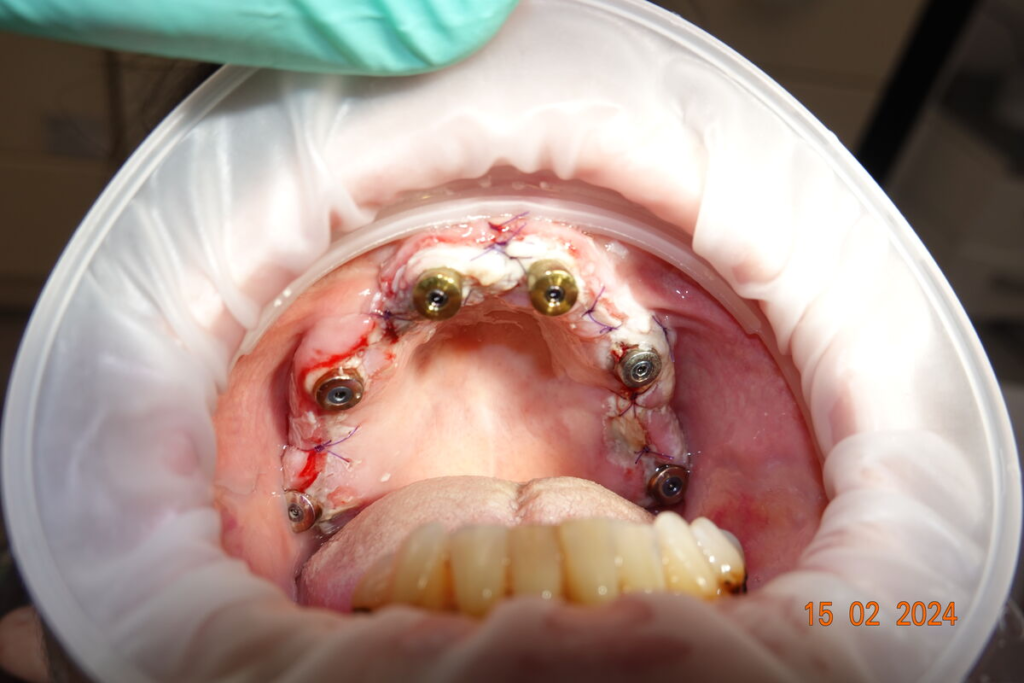

2. Chirurgický den

- případné vytažení zubů a implantace v jeden den

- 4–6 implantátů metodou All-on-X

Technika All-on-X — I. fáze